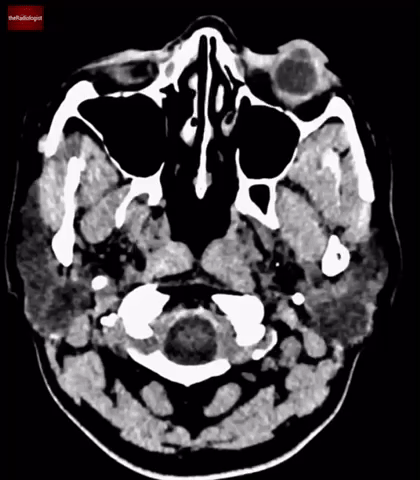

• One of the key uses of MRI in these cases is to use diffusion-weighted imaging (DWI) to help differentiate between malignancy and infection.

• In abscesses, the presence of pus restricts water molecule movement, causing the lesions to appear bright on DWI.

• In this case, the lesions show free diffusion, with no increased signal on DWI. This finding points away from an abscess as the cause.

In this case we can see the centre of the lesions are low signal on DWI meaning there is ‘free diffusion’ pointing away from abscess formation.